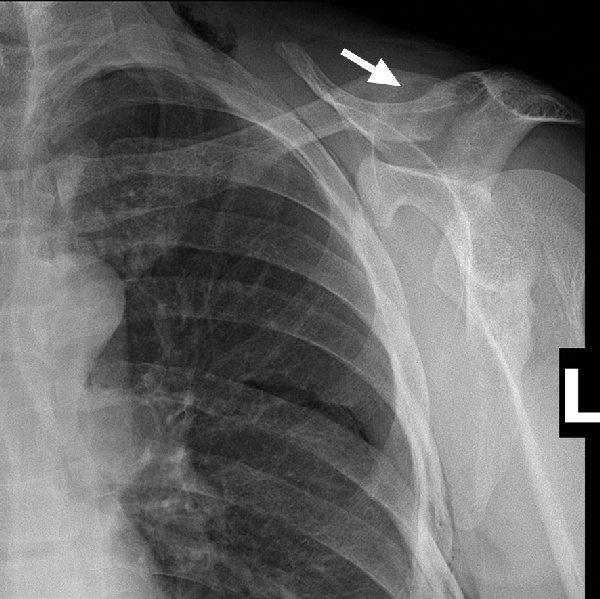

A 45-year-old man with no significant past medical history presented with a fractured clavicle and evidence of a radiolucent lesion (brown tumour) within the clavicle on x-ray, characteristic for hyperparathyroidism (Box 1). On further investigation, biochemical analysis showing raised serum calcium and parathyroid hormone (PTH) levels confirmed primary hyperparathyroidism. A thyroid ultrasound showed a 39 × 29 × 32 mm mass in the right lobe, suggestive of a tumour. A staging computed tomography (CT) scan of the neck and chest and a bone scan showed bone changes consistent with hyperparathyroidism throughout the axial and appendicular skeleton. There was no evidence of metastatic disease.